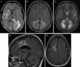

Tumefactive multiple sclerosis

Tumefactive multiple sclerosis is a condition in which the central nervous system of a person has multiple demyelinating lesions with atypical characteristics for those of standard multiple sclerosis (MS). It is called tumefactive as the lesions are "tumor-like" and they mimic tumors clinically, radiologically and sometimes pathologically.These atypical lesion characteristics include a large intracranial lesion of size greater than 2.0 cm with a mass effect, edema and an open ring enhancement. [Source: Wikipedia ]